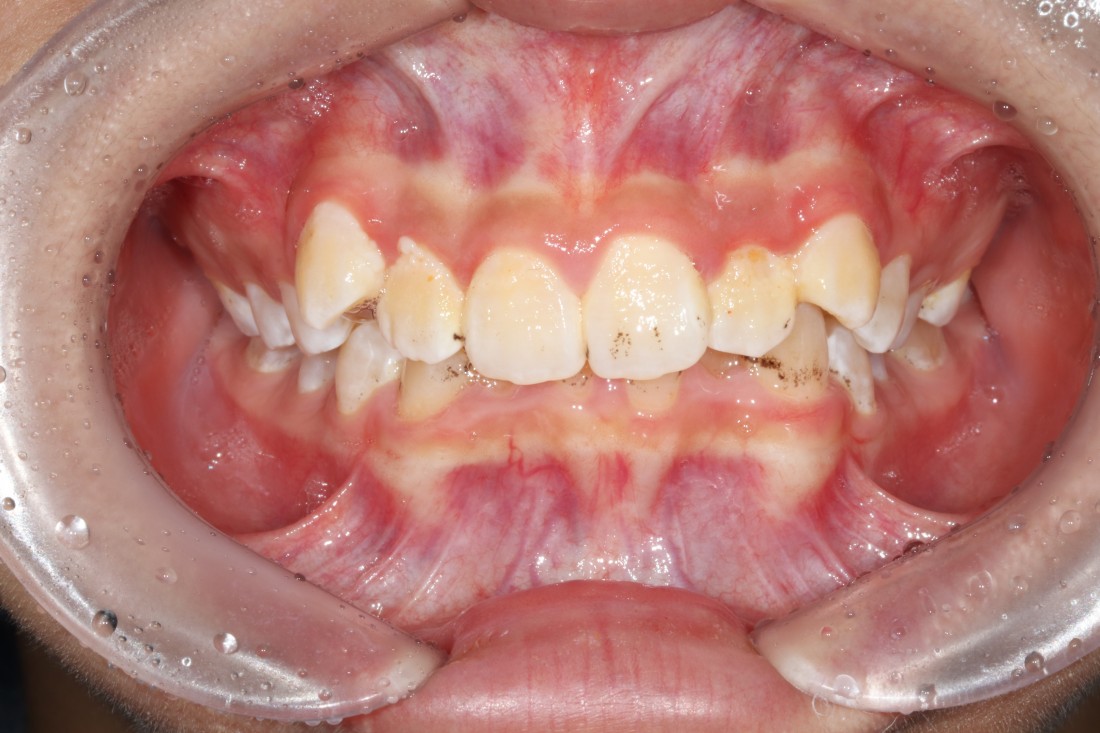

10대 청소년 학생들을 만나다보면

다른 사람들과 마주치거나 대화하는 것도

불편해하는 경우들이 보이는데요.

교정진료 역시 조용한 공간에서

프라이빗하게 받고 싶어하는

경우들이 더 많은 것 같습니다.